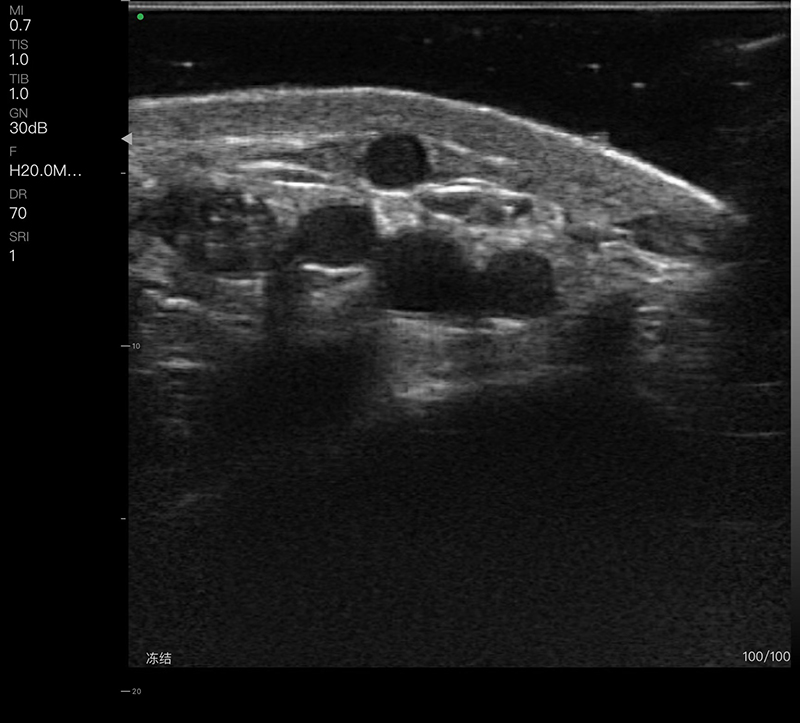

• 探头频率:线阵7.5/10MHz,高频线阵16/20MHz

• 扫描深度:20/40/60/80mm可调

• 扫描宽度:线阵40mm,高频线阵25mm

• 显示模式:B、B/M、Color、PW、PDI